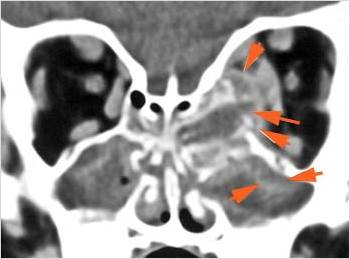

Orbits

The extraconal orbital fat is abnormal. [Yes/No]

There is a subperiosteal abscess or edema along the medial wall, roof or floor of the orbit. [Yes/No]

The extraocular muscles are swollen or otherwise abnormal. [Yes/No]

There is bone erosion along the walls of the orbit. [Yes/No]

The intraconal orbital fat is infiltrated. [Yes/No]

The orbital apex and the superior and inferior orbital fissures are infiltrated. [Yes/No]

The superior and/or inferior ophthalmic veins are dilated or thrombosed. [Yes/No]